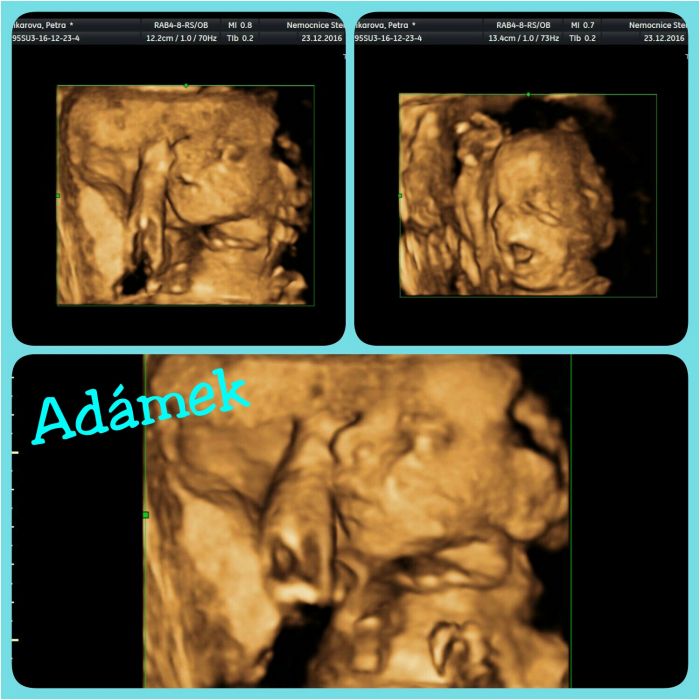

Ahoj holky. Já jdu na kontrolu ve čtvrtek, tak jsem taky zvědavá jestli už je prcek otočený. Ale tím jak mě pořád šťourá pod pravým žebrem tak si myslím že jo, už je to fakt kolikrát nepříjemný :) Už i vím jaký to je když pálí žáha, vzbudilo mě to v noci. My jsme byli na 3D ve 25.tt a prcek se ukázal hezky :) Cukrovku naštěstí nemám, ale myslím si že těch pár týdnů do konce už by se to dalo i vydržet :) Utíká to jako voda. Přidávám foto pupíku a z toho 3D.